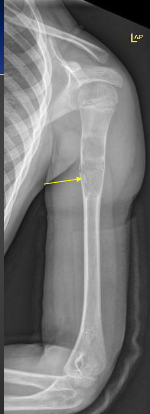

Most common area for Osteochondroma?

-Knee and the humerus

-Adjacent to growth plates and pointing away from articulations

Imaging Features of Osteochondroma

-Corticomedullary continuity

-Pedunculated (thin stalk with large distal cap that is covered in hyaline cartilage)

-Sessile (Broad based osseous excrescence with possible overlying cartilaginous cap)

-Potential sign of accommodation of adjacent osseous structures or signs of soft tissue irritation

Pedunculated Osteochondroma on X-ray

Sessile Osteochondroma on X-ray